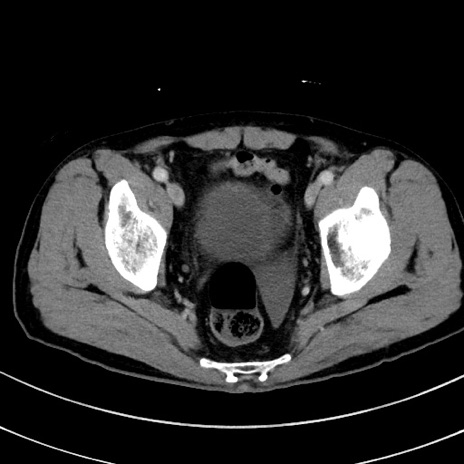

症例8(横断像)

【症例】 60歳代男性

【主訴】 黒色吐物

【現病歴】 4日前から嘔気自覚、2日前の朝食後にも嘔気あり、自分で手で嘔吐反射起こし嘔吐したところ血が混ざっていたため受診。

【既往歴】 5年前汎発性腹膜炎を伴う急性虫垂炎で手術、高血圧、前立腺肥大症、高脂血症

【身体所見】 腹部正中に手術癩痕あり 腹部平坦・軟圧痛なし膨満感あり

【データ】WBC 8400、CRP 4.54